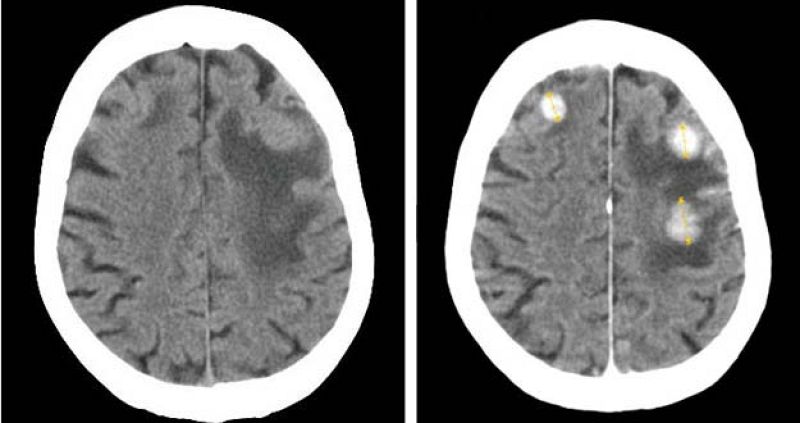

- Es una proteína primordial en activar los procesos involucrados en el daño cerebral

- Se trata de una nueva estrategia terapéutica ante el ictus